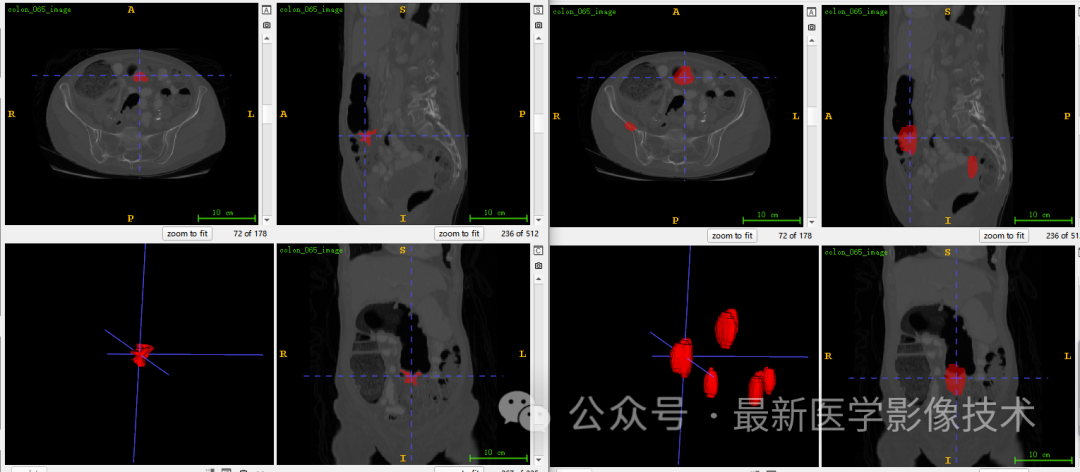

5、验证集分割结果

左图是金标准结果,右图是预测结果。